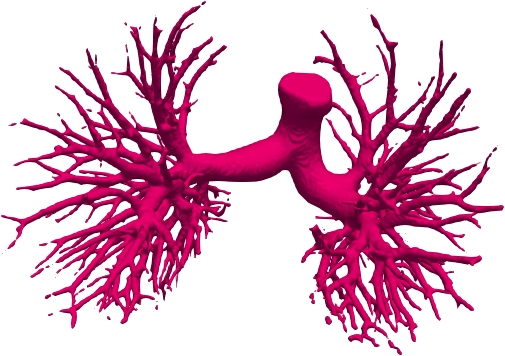

Comparison on PARSE22 dataset. This dataset is more challenging due to more dense small bronchioles shown in supplementary Fig. 6. However, our method still reaches the best weighted average multi-level dice of 84.96% in Table 2 compared against some advanced methods via the official evaluation. As you can see, the remarkable gain comes from the “branch artery”, which maintains the consistency with above airway segmentation.

We qualitatively analyze our method on four challenging lung organ datasets. In Fig. 5, SFCN [19] suffers from severe false positives and some false negatives, especially for the big green areas of airway leakages. WNet [22] is mainly influenced by false negatives on the main trachea. For the Fibrosis dataset at the third row, it also encounters the false negative problem in the terminal bronchioles moderately. FANN [10] bears the slight discontinuity issue of false negative in the terminal bronchioles of BAS dataset, and the severe discontinuity and airway leakage problems on the more challenging Fibrosis benchmark. Instead, due to the above two novel modules, our method can solve the defects of false negative, discontinuity, and leakages faced by past advanced methods. Besides, the results on PARSE22 artery dataset in supplementary Fig. 6 also proves this.